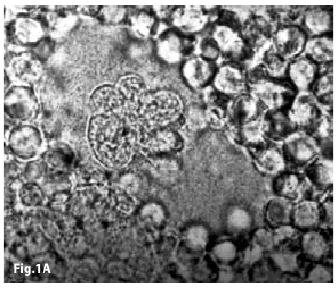

Figure1A